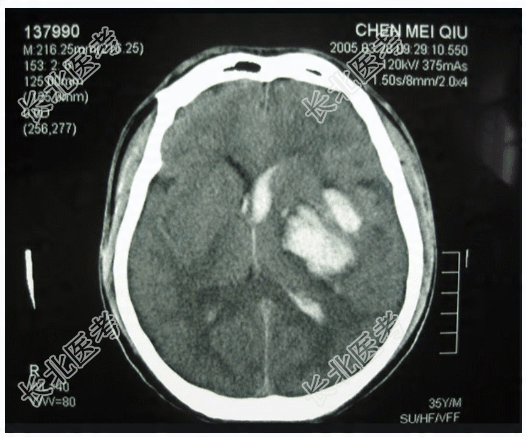

- 多项选择题1.提示:CT片,见下图。可得出的诊断有

A、左侧颞叶脑挫裂伤

B、脑室内出血

C、左侧颞叶脑内血肿

D、左侧颞叶胶质瘤

E、弥漫性脑水肿

F、胶质母细胞瘤